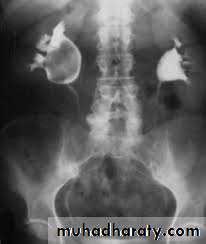

A. First a plain x-ray of the abdomen is taken before the injection of the contrast media, also known as A KUB (kidney, Ureter and Bladder). Calcification & stones may be obscured & missed by contrast media if plain film not takenfirst .B. Films taken after injection of contrast’ medium:

Interpretation of IVU films (what to look for?):

The kidneys:Check their position (left kidney is usually higher).

Identify the whole of both renal outlines, look for any indentations or bulges:

Renal parenchymal width should be uniform(2-2.5cm)

measure renal lengths:

Normal length of adult kidney at IVU is 10-16cm. This is higher than in ultrasound due to image magnification.